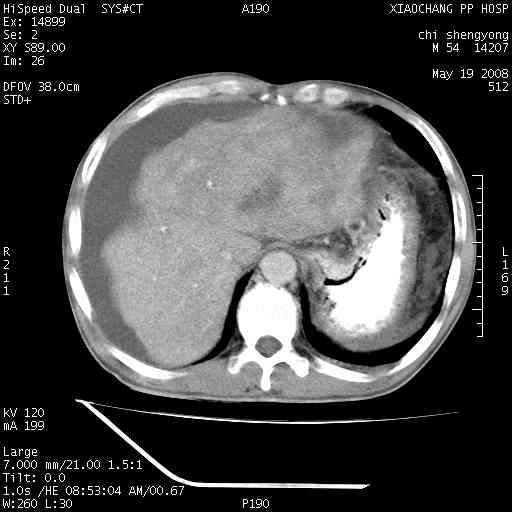

以下是引用zjzjr在2008-5-21 10:52:00的发言:[br]肝左叶巨块型肝癌伴门静脉左支瘤栓形成.肝硬化、腹水,胃底静脉曲张,脾术后改变。

以下是引用随光逐影在2008-5-21 16:20:00的发言:[br]1)肝左叶肝癌伴门静脉左支瘤栓形成,腹膜后淋巴结转移。2)肝硬化、腹水、胃底静脉曲张。3)胆囊炎。4)脾脏缺如,为切除术后所致。